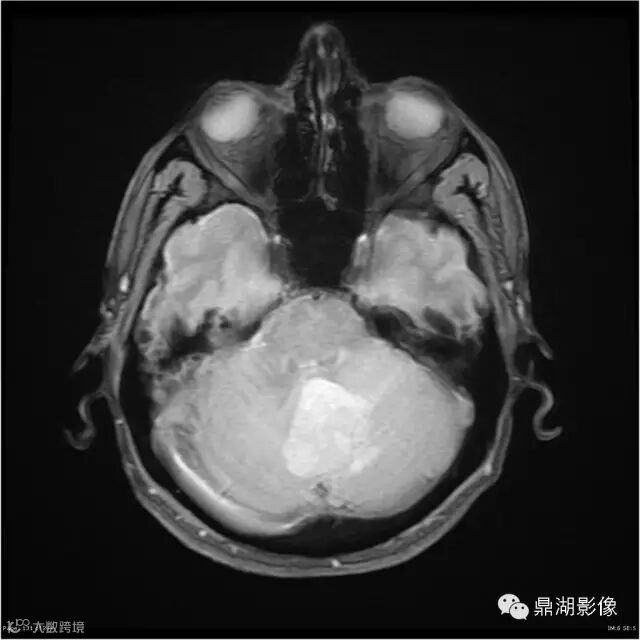

影像:可见一个约43 x 36 x 31mm的从小脑蚓部延伸而来的占位,T1WI、T2WI呈高低混杂信号,病灶周边见流空血管影及水肿带,增强病灶明显强化,中心见无明显坏死区,它紧靠左小脑幕上。第四脑室受压变窄,室管膜水肿,可见脑桥及延脑扁桃体进入枕骨大孔。

本例为一例实质性血管母细胞瘤。实性血管母细胞瘤CT平扫示病灶呈等或高密度,增强后可见明显强化。MRI平扫通常病灶很不均质,T1呈稍低信号为主的较混杂信号,T2呈等、高信号,DWI通常呈低信号或等信号。文献报道,实性血管母细胞瘤较典型的表现为瘤内及瘤周扩张的流空血管影,瘤周中、重度水肿。因此,小脑半球区的单发肿块伴流空血管影,周围大片水肿以及增强后肿块明显强化"形态规则"边界清楚,此时应将实性血管母细胞瘤考虑在内。